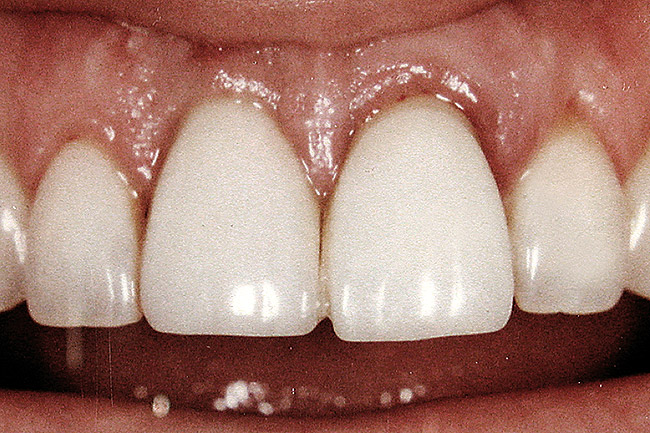

Figure 7  Because the interproximal crestal bone was maintained and the soft tissue supported at the time of tooth removal, an excellent interimplant papilla exists.

Figure 7

Figure 8  Maintenance of interproximal crestal bone following final restoration placement.

Figure 8

Figure 9  The final restorations exhibit a minimal 1-mm to 1.5-mm change in papilla height when compared with the pre-extraction height.

Figure 9